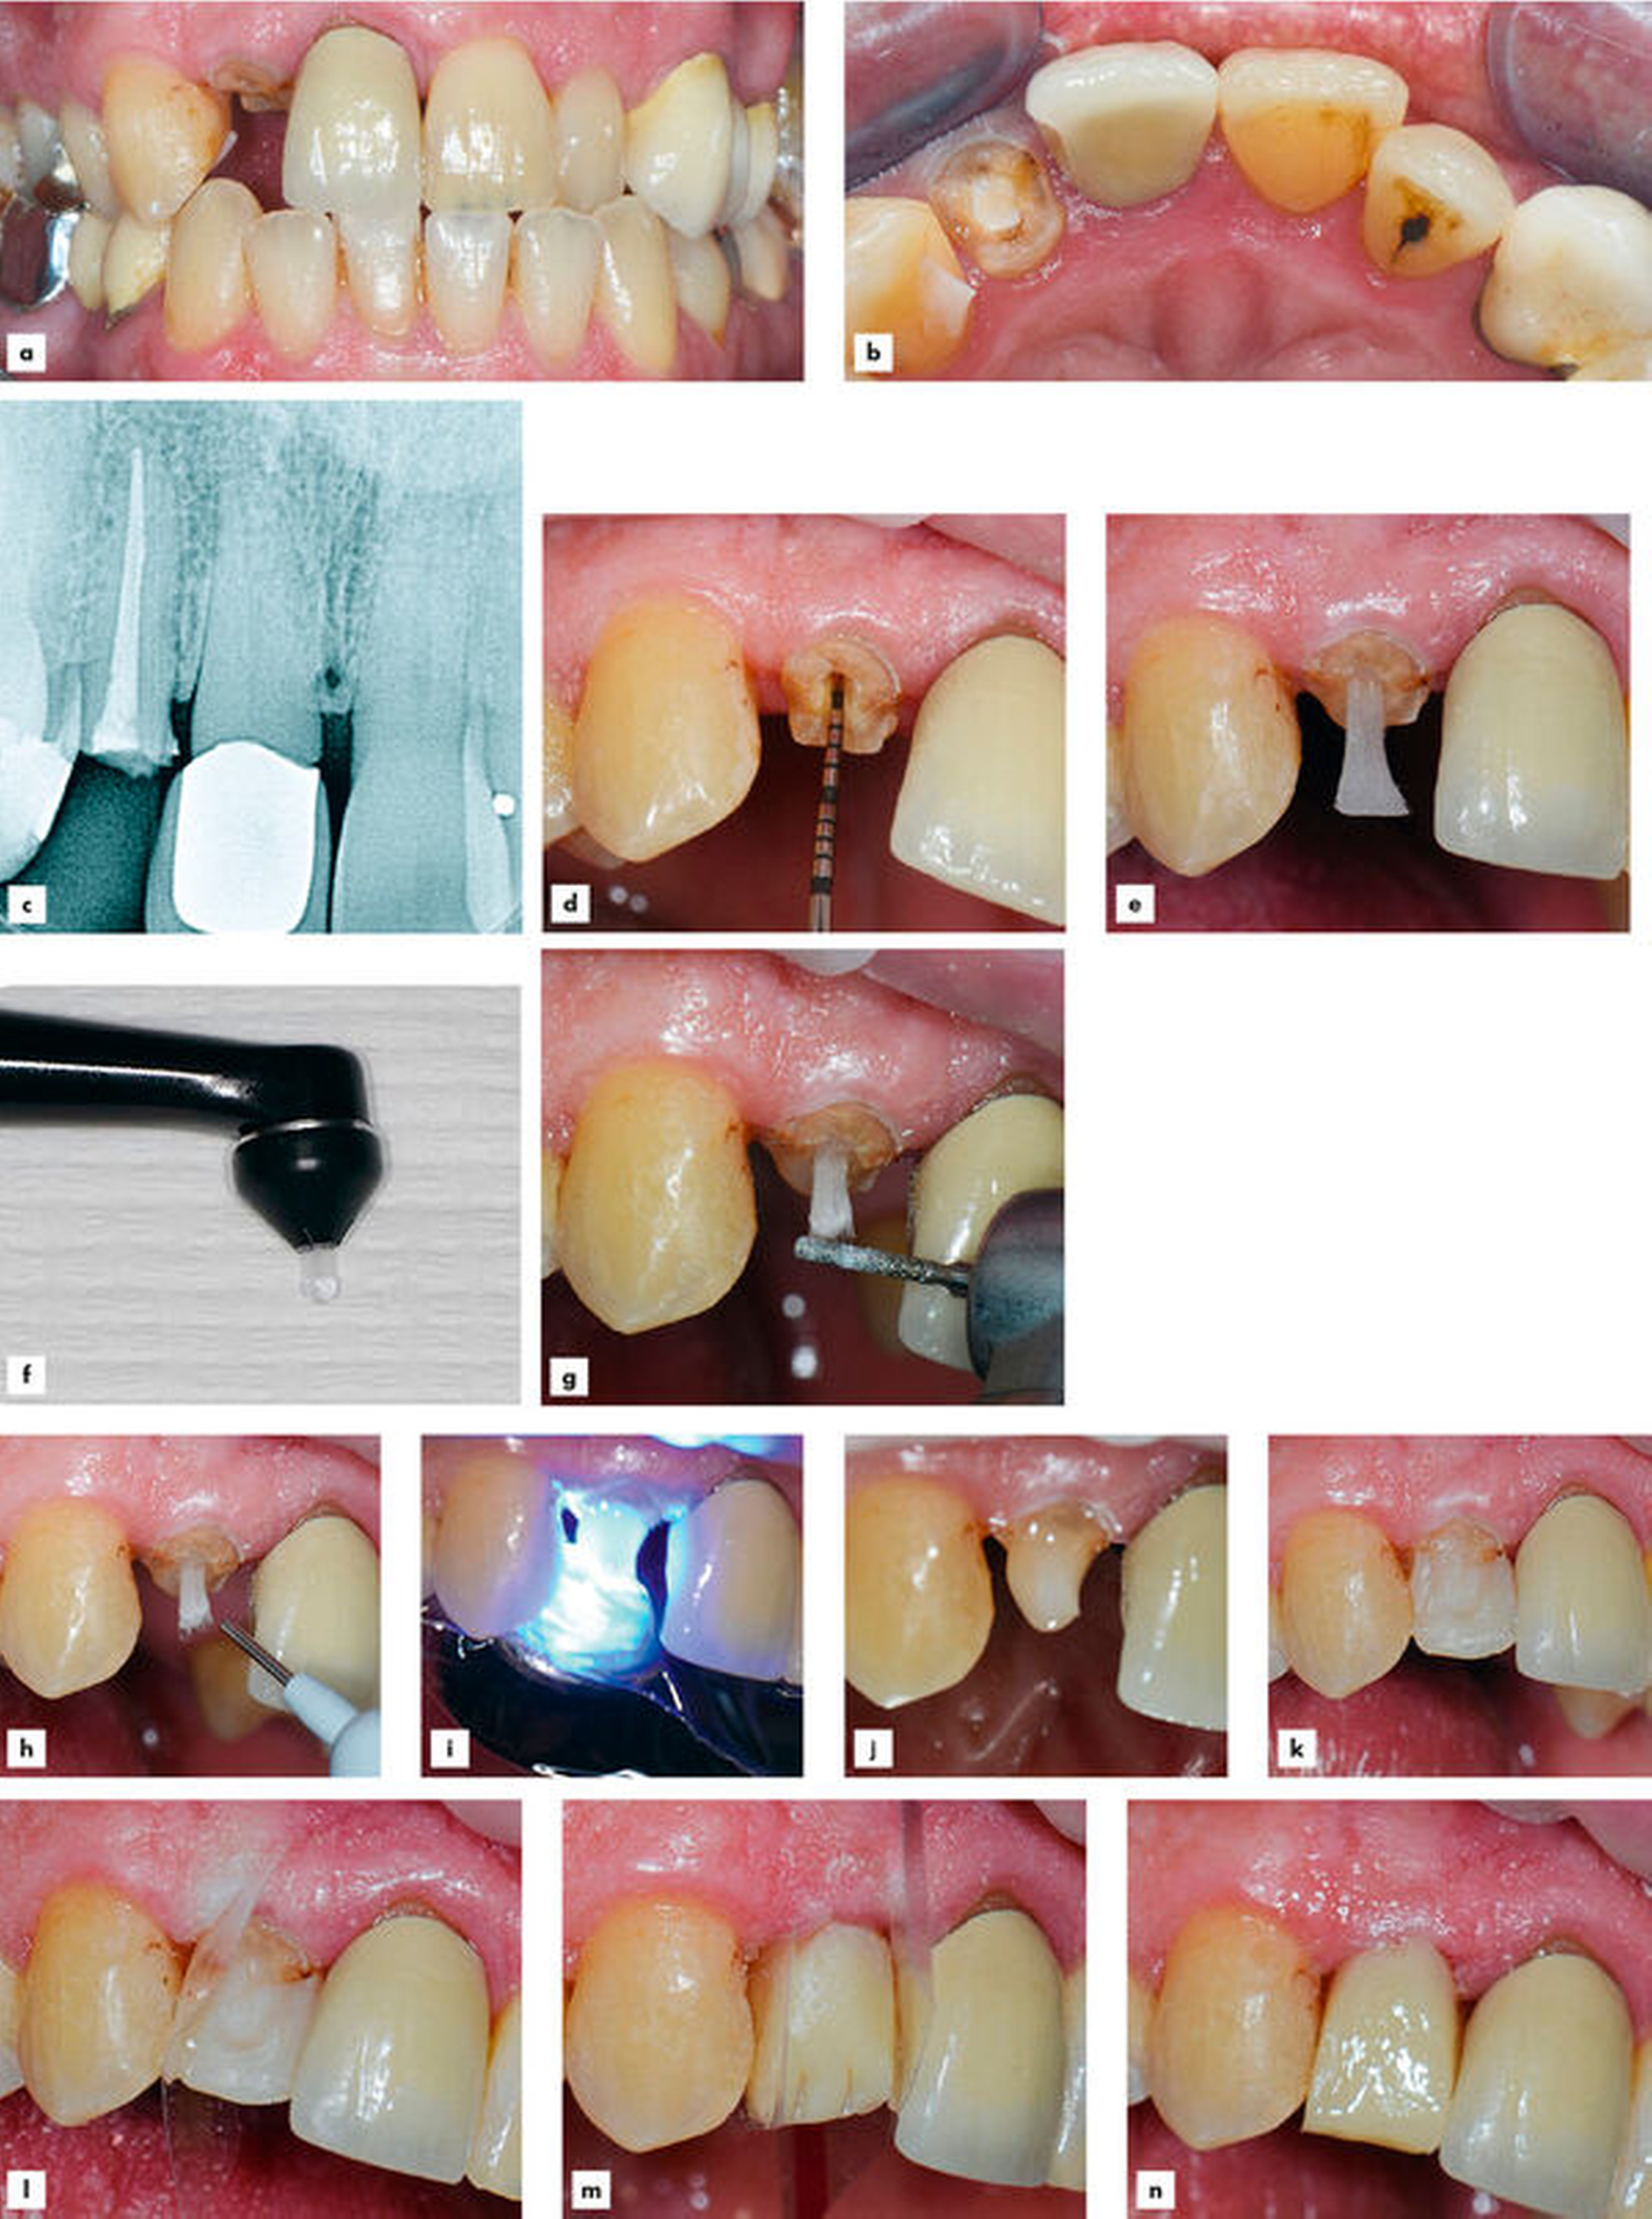

Ein 34-jähriger Lehrer stellte sich bei Nichtanlage der seitlichen Schneidezähne im Oberkiefer mit persistierenden Milchzähnen 52 und 62, die zur besseren Retention mittels Komposit mit den Zähnen 11 und 21 verblockt waren, in der Poliklinik für Zahnerhaltungskunde der Klinik für Mund-, Zahn- und Kieferkrankheiten des Universitätsklinikums Heidelberg vor (Abbildung 1a). Die Zähne 11 und 21 waren nach einem unkomplizierten Frontzahntrauma im Jugendalter mit Kompositrestaurationen versorgt worden. Bei der Erhebung der allgemeinen Anamnese gab der Patient keine Allgemeinerkrankungen an, er rauchte nicht und nahm keine Medikamente ein. Zum Zeitpunkt der Erstvorstellung hatte er keine Schmerzen und keine erhöhten Sondierungstiefen. Die Verblockung zwischen den Zähnen 11 und 52 war gebrochen und es bestand Lockerungsgrad II an Zahn 52 (Abbildung 1b, siehe Pfeil). Die Wurzeln der persistierenden Milchzähne 52 und 62 stellten sich bei röntgenologischer Abklärung als resorbiert dar. Der Röntgenbefund der Zähne 11 und 21 zeigte eine unauffällige periapikale Region sowie koronale Opazitäten im Sinne von Kompositrestaurationen. (Abbildung 1c). Die mesio-distale Breite der persistierenden Milchzähne 52 und 62 betrug circa 4 mm.

Die wichtigsten für die faserverstärkten Kompositbrücken verwendeten Materialien sind in Tabelle 2 aufgeführt. Es wurden Situationsmodelle hergestellt und die zu ersetzenden Milchzähne wurden auf dem Modell radiert (Abbildung 1d). Anschließend wurden zwei Pontics aus Komposit hergestellt (Abbildung 1e). Zur Aufnahme des faserverstärkten Kompositstrangs wurden in die palatinale Fläche der Pontics mit einem birnenförmigen Diamanten Rillen präpariert (Abbildung 1f) und die gesamte Palatinalfläche wurde mit Aluminiumoxidpulver (27 µm Korngröße) abgestrahlt. Da es die Okklusion erlaubte, mussten die Pfeilerzähne 11 und 21 palatinal nicht präpariert werden.

Herstellung der einflügeligen faserverstärkten Kompositbrücken

Nach Infiltrationsanästhesie wurden die Verblockungen der persistierenden Milchzähne gelöst und die Milchzähne vorsichtig entfernt (Abbildung 2a). Bei stehender Blutung konnte Kofferdam zur absoluten Trockenlegung gelegt werden. Die vorbereiteten Pontics wurden gereinigt und das Adhäsivsystem wurde appliziert und lichtgehärtet (Abbildung 2b). Die für das Einkleben vorbereiteten Pontics lagerten bis zu ihrer Verwendung in einem Lichtschutzgefäß. An den Zähnen 11 und 21 wurden die Reste der Verblockung entfernt. Die Zahnoberflächen wurden mit Phosphorsäure angeätzt, abgespült, getrocknet. Anschließend wurden Primer und Adhäsiv aufgetragen. Nach Lichtpolymerisation wurden die vorbereiteten Pontics positioniert und mithilfe einer kleinen Menge Flowkomposit im Interdentalraum (Abbildung 2c) in ihrer Endlage fixiert (Abbildung 2d). Zu beachten war, dass das Pontic im Hinblick auf die Ästhetik und die Reinigungsfähigkeit während der Polymerisation unter Druck in Kontakt zum Kieferkamm kam – eine Wiederholung der Prozedur zur Korrektur der Position wäre jederzeit möglich gewesen.

An den positionierten Pontics wurde nun die Länge des benötigten Faserstrangs mit einer Parodontalsonde ausgemessen (Abbildung 2e). Um beim Abtrennen des Fasermaterials ein Auffasern zu vermeiden, sollte es in seiner Schutzverpackung verbleiben. Zum Befestigen der faserverstärkten Kompositstränge wurde mit einer Sonde eine weitere kleine Menge Flowkomposit auf die palatinale Fläche der Pfeilerzähne und der Pontics aufgetragen. Der zurechtgeschnittene faserverstärkte Kompositstrang wurde darin eingebettet und mit einem Modellierinstrument vorsichtig Schritt für Schritt angedrückt (Abbildung 2f). Hierbei erfolgte die initiale Fixierung des faserverstärkten Kompositstrangs durch kurzes Lichthärten an jeder Stelle (circa drei bis fünf Sekunden). Nachdem die endgültige Position erreicht war), wurde das Fasermaterial vollständig lichtgehärtet und anschließend mit viskösem Kompositmaterial abgedeckt (Abbildung 2g). Diese Überschichtung war unerlässlich, um Feuchtigkeitszutritt und Hydrolyse des faserverstärkten Kompositmaterials zu vermeiden. Die Kompositrestauration an Zahn 11 wurde im Rahmen dieser Sitzung ebenfalls in Form und Farbe korrigiert.

Die Ausarbeitung der Interdentalräume und der Übergänge erfolgte mit einem sichelförmigen Skalpell (Nr. 12). Um Belastungsspitzen auf dem Pontic zu vermeiden, wurde es aus der dynamischen Okklusion genommen, lediglich leichte statische Okklusionskontakte wurden belassen. Die abschließende Ausarbeitung und Formgebung erfolgte mit Finierdiamanten und einem Brownie (Abbildung 2h), die Hochglanzpolitur mit drei Silikonpolierern, wobei letzterer hier abgebildet ist (Abbildung 2i).

Um weitgehend entzündungsfreie Verhältnisse gewährleisten zu können, wurden in einem letzten Schritt Zahnzwischenraumbürsten entsprechend der Größe der neu entstandenen Zwischenräume individuell ausgesucht. Die korrekte Handhabung wurde dem Patienten eingehend demonstriert.

Kontrolle nach zwei Monaten

Bei einer Kontrolle nach zwei Monaten zeigte sich das Erscheinungsbild im Vergleich zum Ausgangsbefund ansprechend (Abbildungen 3a–3f). Die faserverstärkten Kompositbrücken unterschieden sich in Farbton und in der Transluzenz nicht von den Nachbarzähnen. Die Sondierungstiefen an den Zähnen 11 und 21 lagen bei 2 mm, es kam nicht zum Bluten nach Sondieren. Der Patient war zufrieden und nutzte täglich die Interdentalraumbürste.